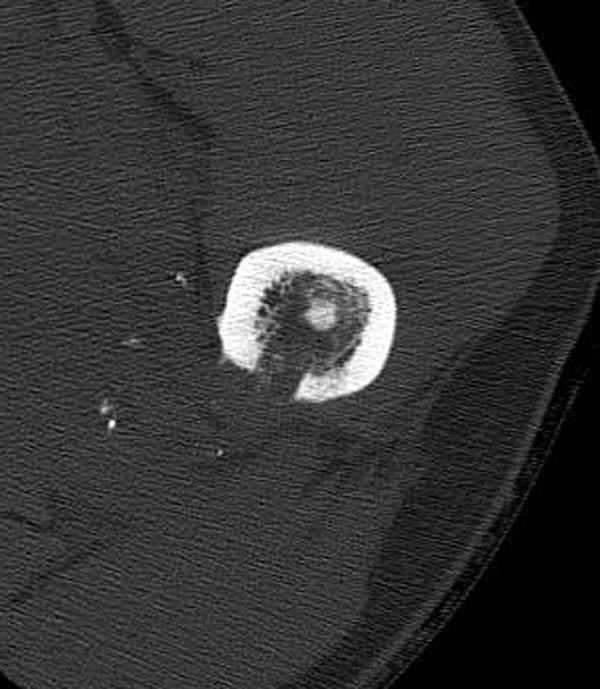

Учитывая, что больной получил травму не во время визита в церковь, и он является одним из представителем 40 миллионного “outstanding itizen”, без медицинской страховки, без работы в свои 39 лет, и без надлежающей ортопедической дисциплины у которого отсутсвует страх стрессового перелома, было рекомендовано оперативное лечение: профилактическое антеградное интрамедуллярное штифтование.

Методика штифтования при отсутствии большой зоны перелома как при онкологических профилактических штифтованиях, расверливание интрамедуллярного канала проводим с предварительным наложением дополнительного дренажного отверстия в дистальном отделе бедра (в данном случаи в канале оставили 6.5 мм канюлированный шуруп), иначе при создании давления в канале во время сверления имеется опасность эмболизации легочной артерии тромбом.